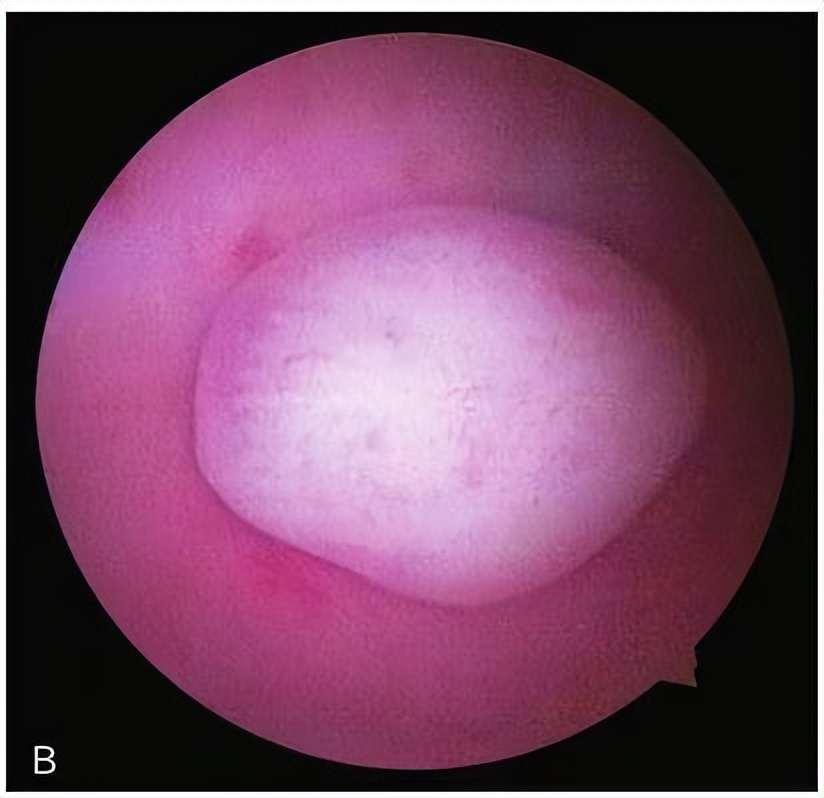

4)B超检查或子宫输卵管造影提示的宫腔占位(子宫内膜息肉、子宫黏膜下肌瘤等);

子宫内膜息肉

子宫黏膜下肌瘤